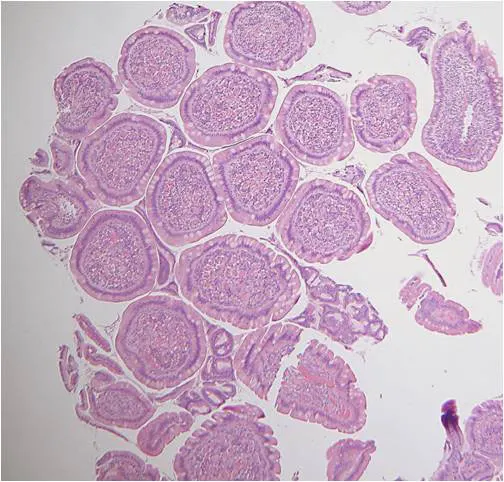

Specimens should be carefully removed from forceps cups with a 25-gauge needle, being careful to position the specimen muscularis side down on a biopsy sponge. Note that biopsy artifacts, such as superficial mucosa and crush artifacts, are inherent in most biopsy procedures regardless of operator experience and technique (Figures 3 and 4).1

This biopsy sample shows duodenal villous tips (eg, “villous slaw”) devoid of subvillous lamina propria and crypts. This artifact may occur when samples are quickly procured using poor biopsy technique or can be caused by improper specimen processing by the pathology service. In this latter situation, tissue sections are cut perpendicular to the villous axis, which makes it impossible to obtain full-thickness mucosal samples for microscopic review.

This figure shows significant crush artifact (circle) of the lamina propria, which obscures mucosal architectural features.